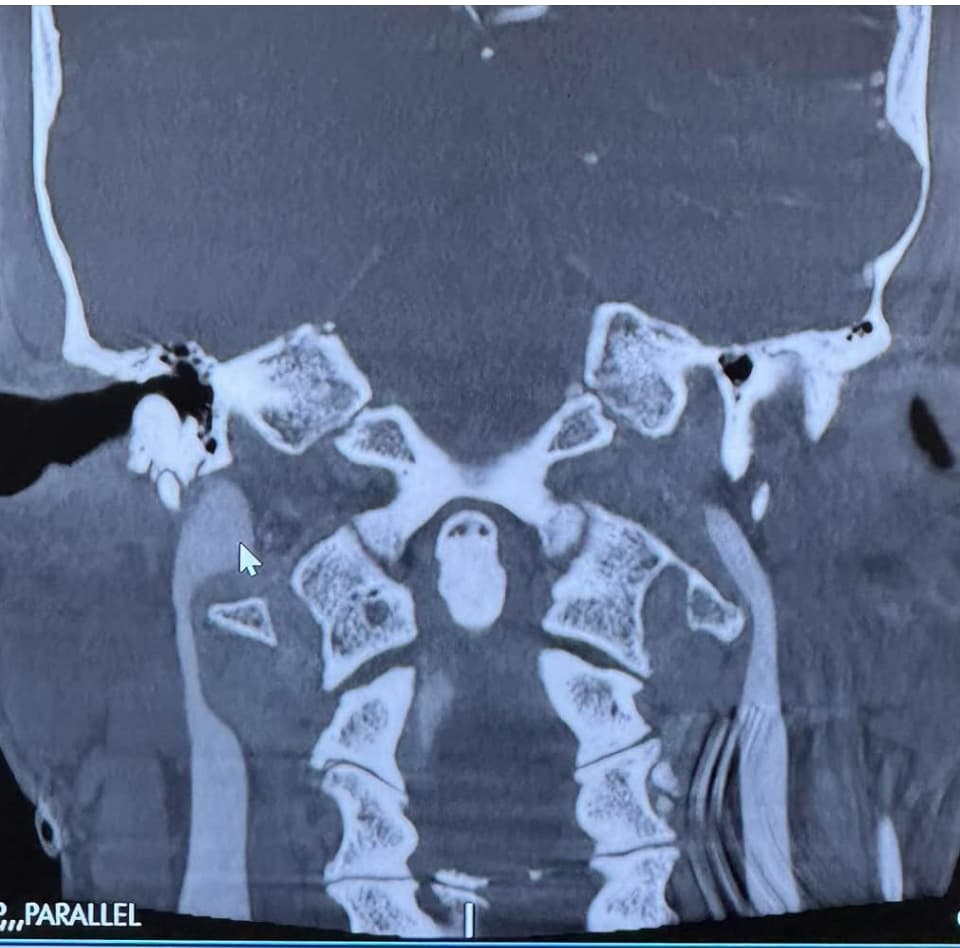

@Johnny99 can you upload an image of C1 in the axial view? I want to see the compression. I know in your previous testing that you lost 100% of an IJV on head rotation. I’ve attached an image of my own C1 in the axial view to help you know what to look for.

If you get me that image of the axial view of your C1 I can help you see the styloid-ijv compression